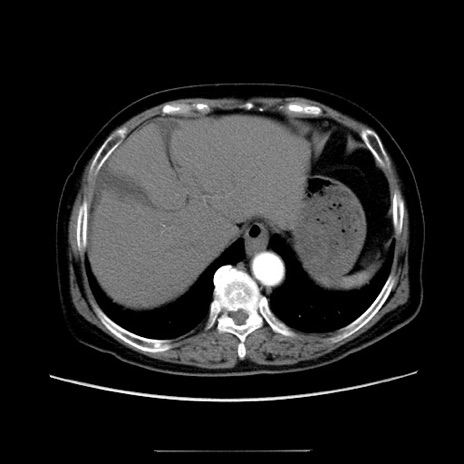

冠状断像

【症例】70歳代女性

【主訴】お腹が張る

【現病歴】1週間くらい前から腹部膨満の自覚あり。昨日夜から増悪したため、本日救急外来受診。

【身体所見】意識清明、BT 36.5℃、BP 165/106mmHg、HR 80bpm、SpO2 98%、腹部:膨満、軟、自発痛・圧痛なし、触診にて不快感あり、腸蠕動音:減弱

【データ】WBC 12600、CRP 1.04